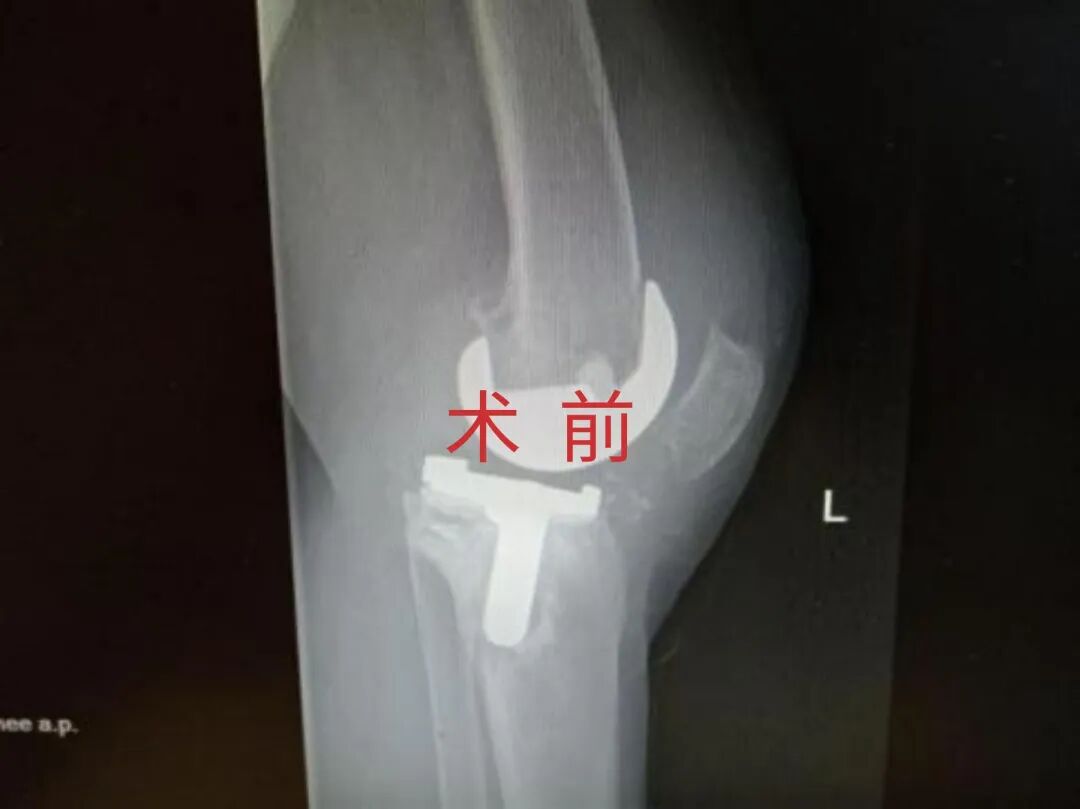

为提升区域内基层医疗机构糖尿病足诊疗服务能力、促进青年医师对糖尿病足的规范化诊治水平,遵义市第二城市医疗集团总院(贵州航天医院)圆满举办贵州省继续医学教育项目——胫骨横向骨搬移技术治疗糖尿病足专题研讨班。 贵州航天医院党委委员、副院长彭亮出席会议并致辞,遵义市第二城市医疗集团各成员单位,以及红花岗区、汇川区、绥阳县、桐梓县等多个区县的基层医疗机构骨干医师参加会议。 研讨班 本次研讨班以胫骨横向骨搬移技术在糖尿病足治疗中的应用为核心主题,围绕糖尿病药物治疗与生活方式管理策略、围手术期血糖精准调控要点、胫骨横向骨搬移技术典型病例深度解析、糖尿病足的临床分型与个体化治疗方案制定等临床实践中的热点与难点展开深入探讨,通过专题授课、案例研讨、互动交流等多元化形式,为参会者搭建了理论与实践结合的学习平台。 此次研讨班不仅为区域内基层医院搭建了学术交流与经验共享的平台,更对推动糖尿病足预防、诊断与治疗的规范化、系统化发展起到了积极作用,有效助力青年医师更新专业知识体系、提升临床技能,为进一步保障区域内糖尿病足患者的健康奠定了坚实基础。 贵州航天医院骨科专家简介 陈明勇 骨一科主任,副主任医师 临床擅长:从事创伤骨科工作约20年,对骨缺损、骨不连、骨肿瘤、肢体畸形等的肢体矫形重建及功能重建,慢性化脓性骨髓炎的根治治疗、糖尿病足的保肢治疗、快速康复理念(ERAS)下的老年骨折的诊治,四肢复杂骨折的诊治,四肢骨折等微创手术治疗具有丰富的临床经验。 2004年毕业于遵义医学院临床专业,曾在中国人民解放军总医院、广西医科大学第一附属医院、上海第六人民医院骨科进修。中国中西医结合学会骨伤科专业委员会横向骨搬移治疗糖尿病足及微血管网再生学组首届委员,遵义市医学会创伤分会常务委员。 瞿 晖 骨科党支部书记,骨二科主任,副主任医师 临床擅长:对骨科的常见病、关节外科、脊柱外科及运动医学疾病的诊治具有丰富的临床经验,熟练掌握骨科手术操作技术。 毕业于遵义医学院临床医学系,2005年前往广州中山大学第一附院骨显微医学部进修学习,2011年前往成都华西医院进修学习,并多次在省内外学习骨科相关知识,是中华医学会骨科分会会员。 赵小锋 中共党员,骨二科副主任,副主任医师 临床擅长:从事骨科临床工作11年,对骨科常见病、多发病诊疗有较为丰富的临床经验,擅长脊柱相关疾病诊断及治疗,尤其是颈、腰、腿疼痛疾病诊断及治疗,擅长胸腰椎骨折微创经皮穿刺内固定术、经皮穿刺椎体成形术、经皮穿刺脊柱内镜下腰椎间盘摘除术、单纯开创腰椎间盘摘除术、腰椎滑脱复位椎间植骨椎融合内固定术、腰椎管狭窄减压融合内固定术及人工髋、膝关节置换术等。 2012年毕业于遵义医学院外科学专业硕士研究生,2019年参加“遵义市115医学人才精英计划”于上海交通大学第一附属医院培训学习,2023年于北京大学第三人民医院脊柱外科进修学习,曾获得遵义市优秀医师荣誉称号。 遵义市手外科第一届委员,遵义市医学会创伤分会第一届委员,遵义市医学会创伤分会第二届委员,贵州省康复医学会第三届脊柱脊髓专业会委员,遵义市医学会烧伤与整形外科学分会委员,发表论文5篇,其中国家级核心期刊1篇,SCI论文1篇,主持市级课题1项并结题,参与市级课题2项。 赵兴东 骨科主任医师 临床擅长:擅长骨科的常见病及各种创伤、四肢骨折创伤修复、骨感染、手足疾病的诊治和手足体表畸形的矫形整复,熟练掌握骨科四肢骨病及创伤的手术操作技术,尤其在四肢关节复杂性损伤、手足外伤、组织缺损创面、难治创面的皮瓣修复方面及平足、高弓足矫形方面及四肢慢性疼痛诊治、康复方面具有丰富的临床经验。 硕士研究生,毕业于遵义医学院临床外科系,2015年前往山东省立医院手足外科进修学习;遵义市医学分会创伤分会第一、二届委员,遵义市手外科医学会第二委届员会常务委员;在省级及省级以上期刊发表文章9篇,参编著作2部,参与主持并完成市级课题1项,参与市级课题2项、省级课题1项。 张艳金 中共党员,骨科副主任医师 临床擅长:从事骨外科工作16年,对复合伤、多发伤的救治、四肢骨干骨折、关节周围骨折、骨肿瘤、骨髓炎等诊治具有丰富的临床经验。 中共党员,硕士研究生,2006年本科毕业于山西医科大学第二临床医学院,2011年研究生毕业于北京军区总医院;在“老年COPD患者合并髋部骨折的诊治”国际合作课题组研究两年,在老年髋部骨折的诊治方面具有丰富的经验,并发表论文6篇;主持遵义市级课题1项,承担遵义医科大学的临床教学工作,获得遵义医科大学优秀带教老师荣誉。编撰有《骨科疾病诊疗精粹》一书,开展2项新技术,编撰地方规范《务川自治县创伤骨科常见疾病诊疗规范》一书。 张俊凯 骨科副主任医师 临床擅长:从事骨科临床工作28年,对创伤骨折、骨感染、骨缺损、骨不连等外科诊治,四肢骨折的微创手术治疗,四肢复杂骨折(如关节内粉碎性骨折、多发骨折等)的损伤控制及手术治疗等具有丰富的临床经验。 1995年毕业于遵义医学院临床专业,2009年前往复旦大学附属医院骨科进修1年。 卢懿明 中共党员,骨科副主任医师 临床擅长:从事骨科工作18年,对创伤骨折、四肢骨折的微创手术治疗、四肢复杂骨折(如关节内粉碎性骨折、多发骨折等)的损伤控制及手术治疗,尤其是髋部骨折的PFNA等微创技术,踝关节骨折、膝关节周围骨折的Mipo微创技术等具有丰富的临床经验,开展了4项新技术,发明6项新型专利技术。 2005年毕业于遵义医学院临床专业,2017年,前往南方医科大学第三附属医院骨科进修半年,回院后运用Mipo技术对骨干骨折及干骺端骨折的治疗技术,同时积极开展骨盆骨折、髋臼骨折腹直肌外侧切口的应用;发表了多篇专业论文,经常参与省内外学术交流会授课,获得医院荣誉称号多个。 邬夏荣 骨科副主任医师 临床擅长:从事骨科工作16年,对四肢复杂骨折、骨肿瘤的诊治,尤其是足踝创伤、慢性踝关节损伤、平足症等诊疗具有丰富的临床经验。 2006年毕业于遵义医科大学临床医学专业,曾在陆军军医大学西南医院进修学习,发表多篇骨科学术论文。 余德怀 中共党员,骨科副主任医师 临床擅长:从事骨科工作10余年,对运动医学、骨关节、脊柱外科常见病、多发病的诊治具有丰富的临床经验。 硕士研究生,2011年毕业于遵义医学院临床医学专业,曾前往遵义医科大学附属医院运动医学专业进修学习;是贵州省医学会运动医学分会青年委员,西部关节镜联盟委员;发表多篇骨科学术论文。 冯 乾 骨科副主任医师 临床擅长:从事骨科工作近20年,熟练掌握骨科多发病及常见病的诊治,尤其对脊柱退变性疾病的诊断及治疗具有丰富的临床经验,主要研究脊柱微创相关治疗方式,能熟练开展椎间孔镜及UBE。 曾前往北京大学第三医院进修学习疼痛及椎间孔镜、首都医科大学友谊医院专业进修脊柱内镜;是贵州省康复医学会第三届脊柱脊髓专业委员会委员;发明专利3项、发表脊柱外科专业论文多篇。 贵州航天医院骨科简介 基本情况 贵州航天医院(原3417医院)骨科组建于1968年,前身是以创伤和断肢(断指)再植闻名于世的上海市第六人民医院骨科,中国断肢(断指)再植的奠基者、中科院院士陈仲伟等专家莅临科室指导医疗和教学,并在70年代开展了贵州省首例断肢(断指)再植手术。组建50余年来,诊治患者已逾百万,挽救了无数的伤病员,成为了保障遵义地区人民群众健康的重要支撑。 经过几代人的不懈努力,今天的骨科,已由创伤骨科发展至骨病、骨肿瘤、骨结核等领域,现有脊柱外科、关节外科、四肢创伤、手足外科四个亚专科,成为了集医疗、教学、科研于一体的综合学科,是贵州省临床重点专科、遵义市临床重点专科、遵义市骨科临床医学中心、遵义市基层骨科专科联盟理事长单位。 科室目前开放床位110张,共有医护人员50余人,副高级以上专家18人,硕士研究生15人。拥有一流骨科医疗设备多台,每年不定期选派优秀技术骨干到全国各大知名医学院校进修、学习、参观、交流,并邀请国内、国外知名专家教授来院进行交流、指导,通过不断引进国内外先进的诊疗技术,科室医疗技术水平稳步提升,为广大人民群众提供了优质的医疗服务。 专科特色 骨一科 (一)骨缺损、骨不连的肢体与功能重建 胫骨横向骨搬移技术治疗糖尿病足: (二)慢性骨髓炎的根治治疗 (三)肢体缺血性疾病如糖尿病足、脉管炎的保肢治疗 (四)皮瓣修复 (五)复杂创伤的治疗 (六)老年髋部骨折及小儿骨折快速手术 老年髋部骨折: 骨二科 (一)胸腰椎骨折微创经皮椎弓根螺钉固定术 (二)老年性骨质疏松性患者腰椎滑脱脊柱内固定术(骨水泥螺钉) (三)V形双通道脊柱内镜技术(VBE)腰椎融合术治疗腰椎退行性疾病 (四)老年性骨质疏松性骨折(PVP/PKP)术 (五)人工髋关节置换术 (六)双侧股骨头坏死人工全髋关节置换 (七)右侧全髋置换术后假体周围骨折翻修 (八)人工膝关节置换术 (九)人工膝关节假体松动翻修 (十)关节镜技术 传统手术切口 关节镜技术切口 诊疗范围 骨一科 1.四肢创伤、矫形。 2.手、足踝外科。 骨二科 End